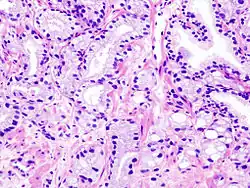

Rak urotelialny w obrębie gruczołu krokowego

Jest to nowotwór pochodzący z nabłonka dróg moczowych w obrębie gruczołu krokowego. Pierwotny rak urotelialny obejmujący stercz stanowi 0,7–2,8% nowotworów tego narządu u ludzi[164]. Zwykle jest związany z pierwotnym rakiem urotelialnym pęcherza moczowego lub urotelialnym rakiem moczowodu. Zajęcie gruczołu krokowego może być związane z szerzeniem się raka urotelialnego do stercza, implantacją nowotworu pochodzącego z pęcherza moczowego lub moczowodu albo następstwem niezależnej wieloogniskowej karcynogenezy raka urotelialnego[165]. Rak urotelialny w obrębie stercza bez obecności raka urotelialnego w obrębie pęcherza moczowego jest rzadki[165].

Większość raków urotelialnych w obrębie stercza jest wysokiej złośliwości i są one związane z rakiem in situ[164]. Typowa jest obecność pagetoidalnego szerzenia się pojedynczych komórek lub zagnieżdżanie się komórek nowotworowych między warstwą podstawną i warstwą komórek wydzielniczych[164]. Przy rozległym naciekaniu rak urotelialny może wypełniać i poszerzać kanaliki gruczołu krokowego[164][165]. Może być obecna martwica typu comedo[165]. Komórki nowotworowe charakteryzują się wyraźnym pleomorfizmem jądrowym, hiperchromazją i obecnością licznych mitoz. W przypadku inwazji podścieliska obecne są nieregularne gniazda lub sznury komórek i wyraźna reakcja desmoplastyczna[164][165].